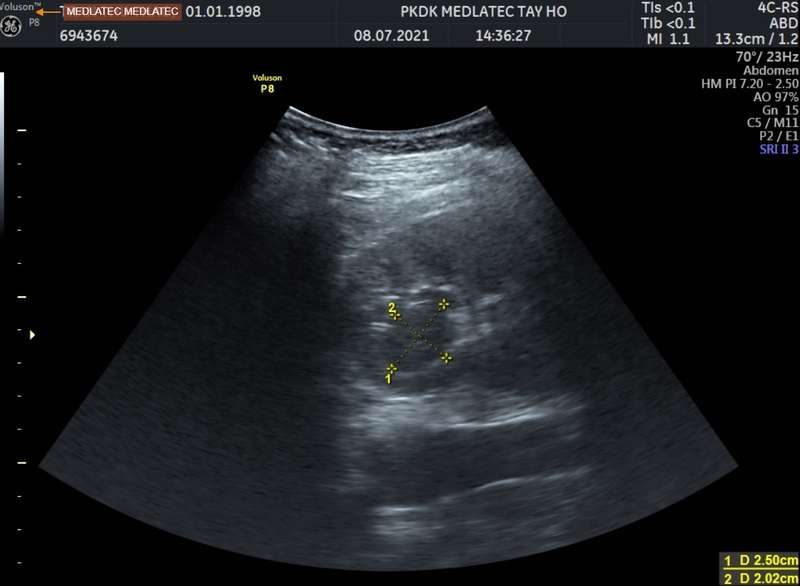

Siêu âm vùng chậu dùng sóng âm thanh tần số cao để tạo ra những hình ảnh bên trong xương chậu. Thông qua phương pháp này, bác sĩ có thể nhìn vào bàng quang, buồng trứng, cổ tử cung, tử cung và ống dẫn trứng của chị em phụ nữ.

Theo bác sĩ chuyên khoa, khi có nghi ngờ bệnh nhân bị viêm vùng chậu dựa trên những triệu chứng lâm sàng, phương pháp siêu âm vùng chậu sẽ được chỉ định để qua đó bác sĩ có thể quan sát, kiểm tra tình trạng của các cơ quan lẫn cấu trúc rắn, đồng nhất của các cơ quan nằm ở vùng chậu.

Bác sĩ dùng đầu dò được di chuyển trên vùng bụng dưới của bệnh nhân để tìm u xơ tử cung lớn hoặc một số vấn đề khác trong khung chậu của cả nam và nữ.

Siêu âm vùng chậu là biện pháp quan trọng để bác sĩ đánh giá cấu trúc của tử cung và buồng trứng ở phụ nữ, từ đó đưa ra chẩn đoán về các vấn đề tiềm ẩn có thể gây ảnh hưởng đến sức khỏe sinh sản, bao gồm:

Siêu âm vùng chậu giúp đánh giá nguyên nhân gây chảy máu hoặc đau bất thường và đưa ra các biện pháp điều trị có mục tiêu.

Phát hiện bệnh viêm vùng chậu (PID) và chẩn đoán thai ngoài tử cung là những khía cạnh quan trọng đối với sức khỏe của phụ nữ được giải quyết thông qua siêu âm vùng chậu.